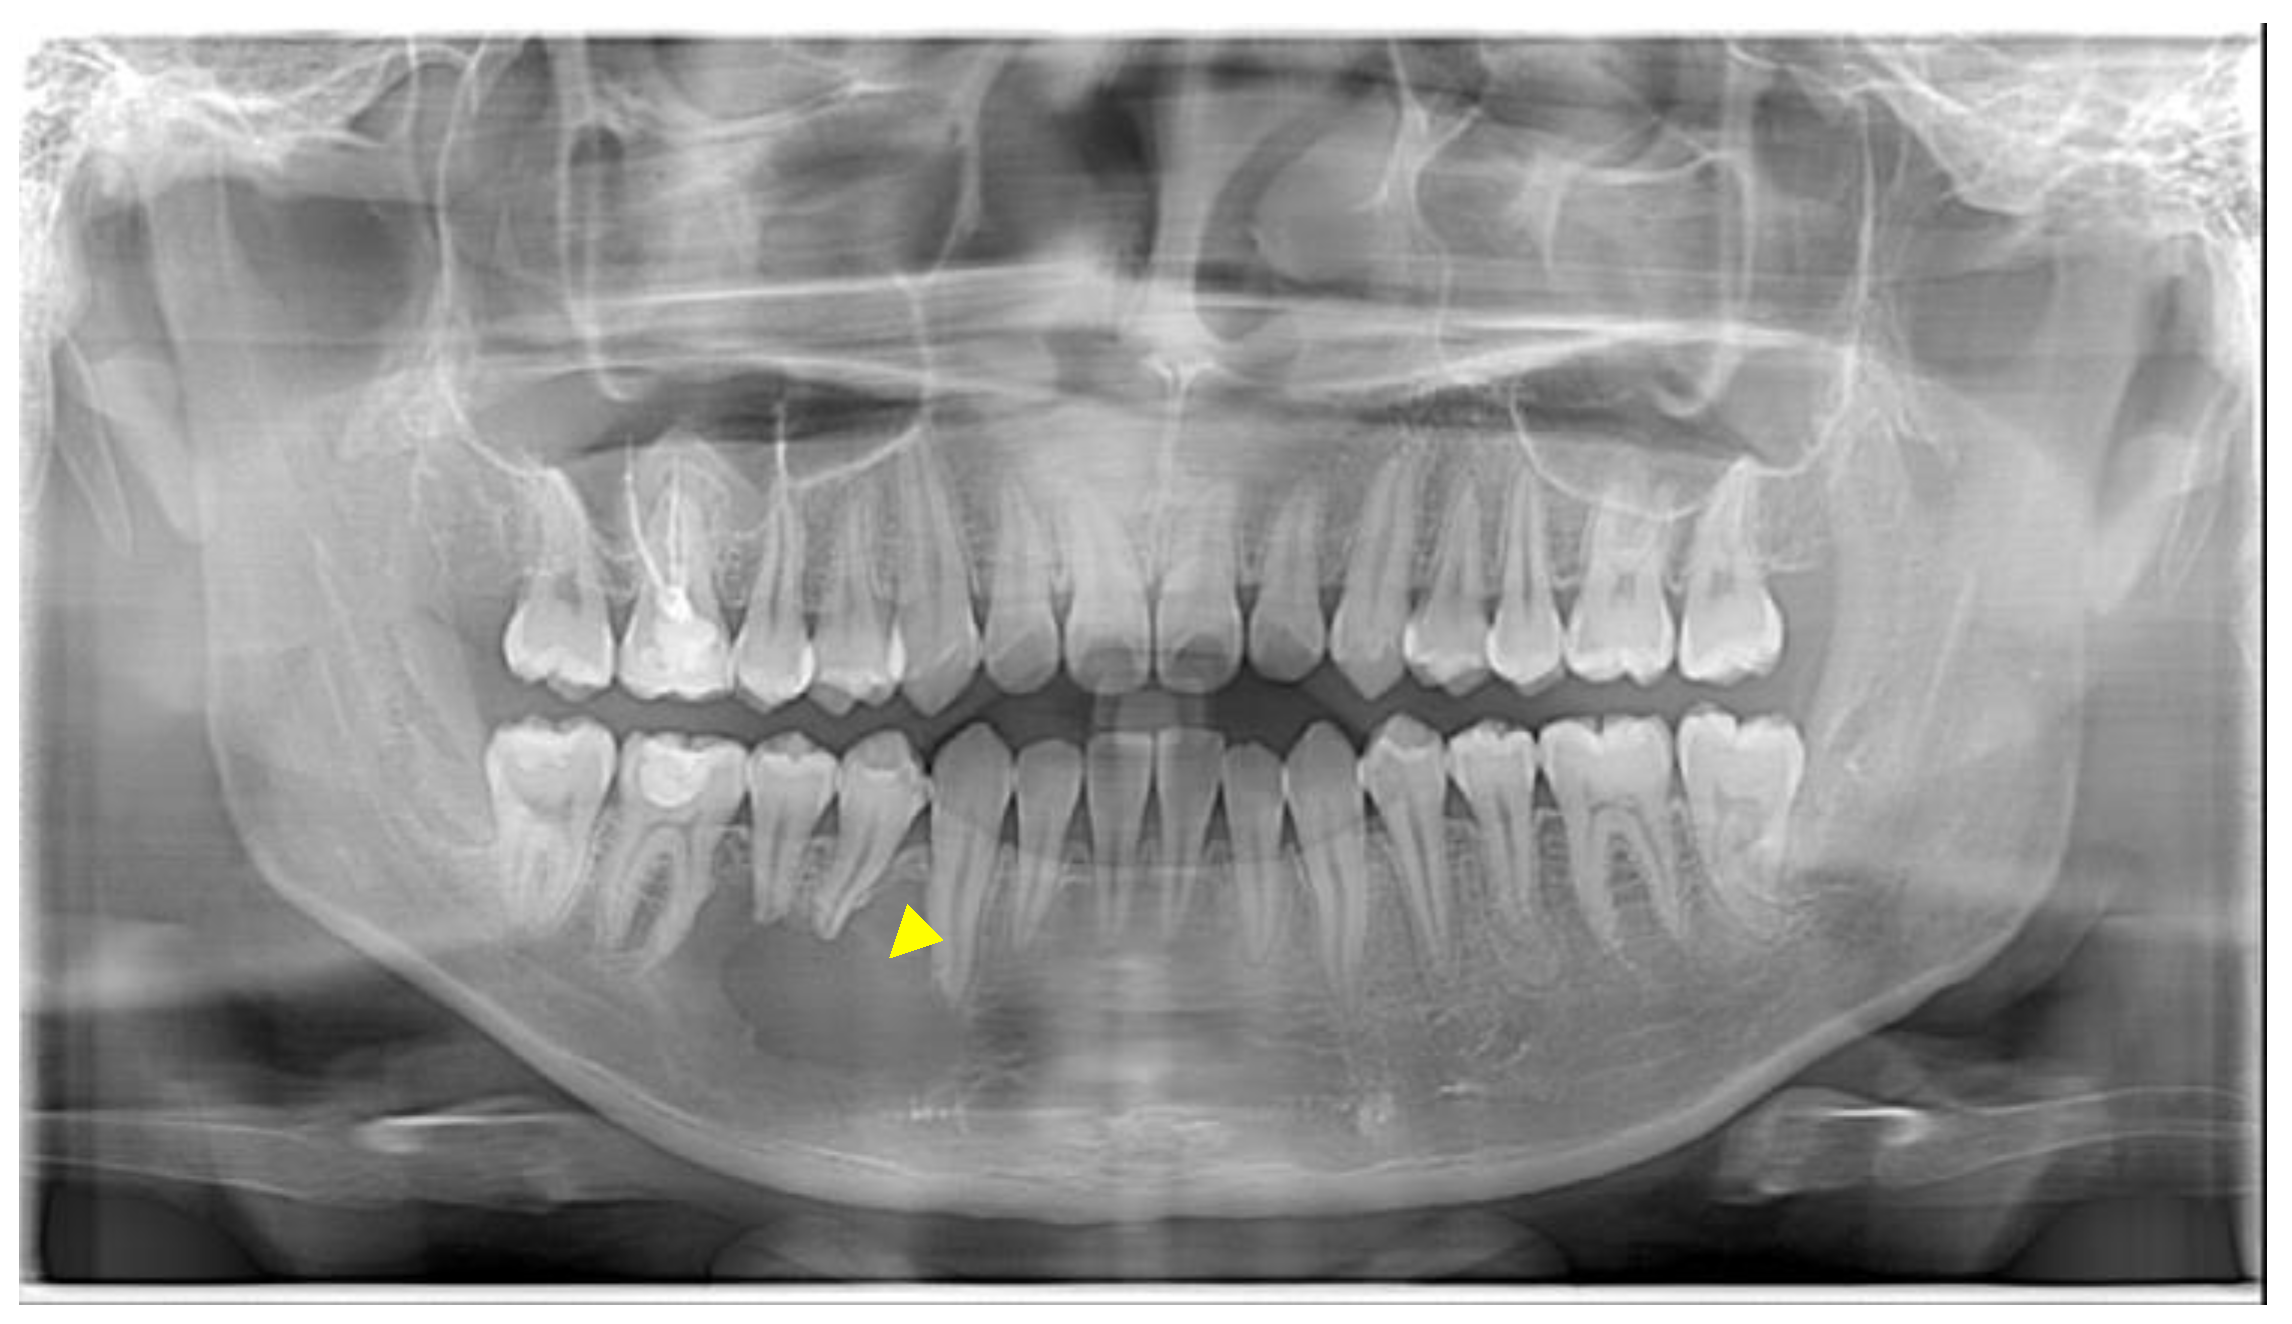

A young male presented in the Urgent Care Clinic at Boston University Henry M. Goldman School of Dental Medicine with a panoramic radiograph, seeking dental care due to numbness in the lower right region of his mandible. His dentist had referred him for a root canal treatment (Figure 1).

A detailed history in the Department of Oral Surgery (OS) revealed that the patient was experiencing pain upon palpation on the right side of the mandible for the past month and discomfort while chewing on the same side for two weeks. His general dentist referred him after noting a moderately sized unilocular, scalloping radiolucency associated with teeth #27, #28, #29, and #30 on the panoramic radiograph. At the OS clinic, the patient underwent a thorough extraoral examination, which showed no sign of swelling, and exhibited a full range of motion of his mandible. Intraoral examination revealed a palpable soft, squishy swelling perforating the buccal cortex in the area of #27–#30 with all teeth in the lower right quadrant evaluated as vital. The neurological assessment revealed intact cranial nerves (CN) V1 and V2, but the right CN V3 distribution in the right chin area exhibited paresthesia.

Radiographic findings were highly suggestive of a unicystic ameloblastoma or, less likely, central giant cell granuloma (CGCG). Typically, CGCGs are characterized by more expansion, with thin and wispy septations [10]; the internal structure, due to reactive histopathological features, shows evidence of grainy and reactive bone [11]. These findings indicated the need for further evaluation with a biopsy to confirm the diagnosis and determine appropriate management. The patient was informed about the findings, treatment plan, and postoperative care, to which he consented.

Figure 1. The yellow arrowhead shows a unilocular lesion detected in the area of #27–30.